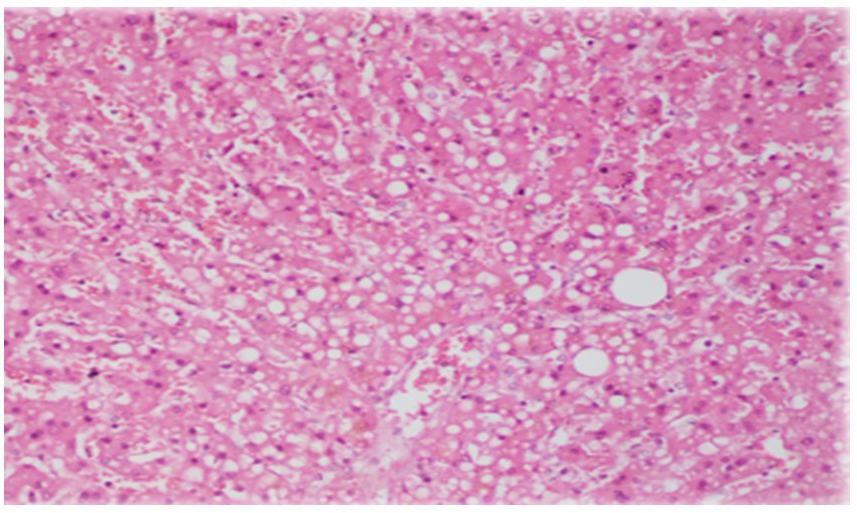

An acute necroinflammatory pattern was the predominant hepatic lesion, observed in 87.0% (n = 486) of cases [Figure 2A and B]. Microvacuolar steatosis (> 5%) was noted in 27.2%, while cholestasis was identified in only 9.3% of cases [Figure 3]. Chronic liver alterations were also frequent: liver fibrosis in 48.5%, SLD in 42.4%, and cirrhosis in 5.2% [Table 1].

Figure 2. Hepatocellular lobular necrosis. (A) Confluent necrosis around centrolobulillary veins; (B) Bridging necrosis (Haematoxylin/Eosin 10×).